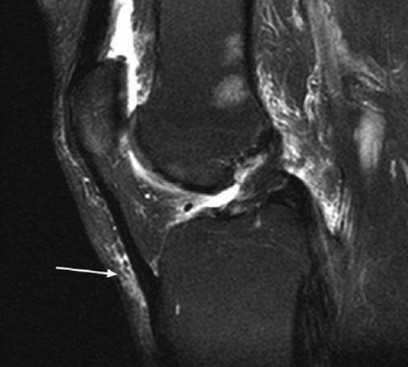

Поверхностная инфрапателлярная сумка расположена между бугристостью большеберцовой кости и вышележащей кожей, тогда как глубокая ограничена задней стороной сухожилия надколенника и большеберцовой костью. Выделяют:

Поверхностный инфрапателлярный бурсит

МРТ коленного сустава: сумка расположена под кожей над бугристостью большеберцовой кости (стрелка)

Поверхностный инфрапателлярный бурсит, также называемый коленом священника, возникает из-за воспаления и накопления жидкости в результате хронического сдавления. Клинически наблюдается ощутимая припухлость ниже коленной чашечки. Изначально боль может отсутствовать.

На МРТ патология выглядит как жидкостное образование, выступающее перед сухожилием надколенника (стрелка)

При визуализации бурсит дифференцируют с подкожным отеком, последний представляет диффузное (не локализованное с четкими границами) депонирование жидкости по всей поверхности колена.

Глубокий инфрапателлярный бурсит

Воспаление глубокой поднадколенниковой сумки на МР-скане (стрелка)

На МРТ глубокий инфрапателлярный бурсит проявляется в виде треугольного скопления жидкости сзади сухожилия надколенника. При обнаружении у подростков воспаленную сумку дифференцируют от болезни Осгуда-Шлаттера, для которой типичны гиперинтенсивность сигнала. Инфрапателлярный бурсит чаще развивается при падении на колени. Патологии подвержены плиточники, строители, горничные.